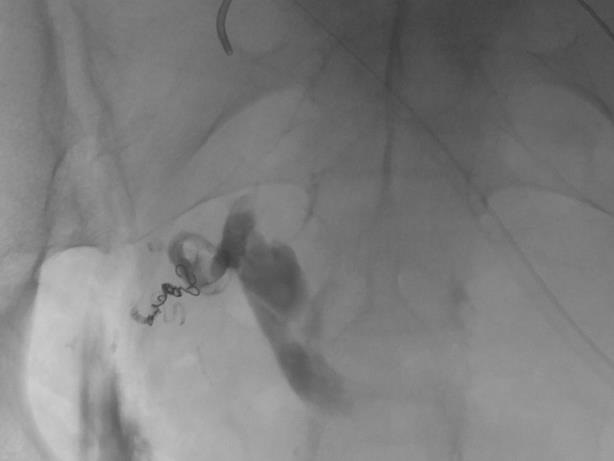

外伤后出血的栓塞

外伤后可见造影剂外溢 |

微导管选择至出血血管 |

出血血管的微弹簧栓子栓塞 |

栓塞后造影 |